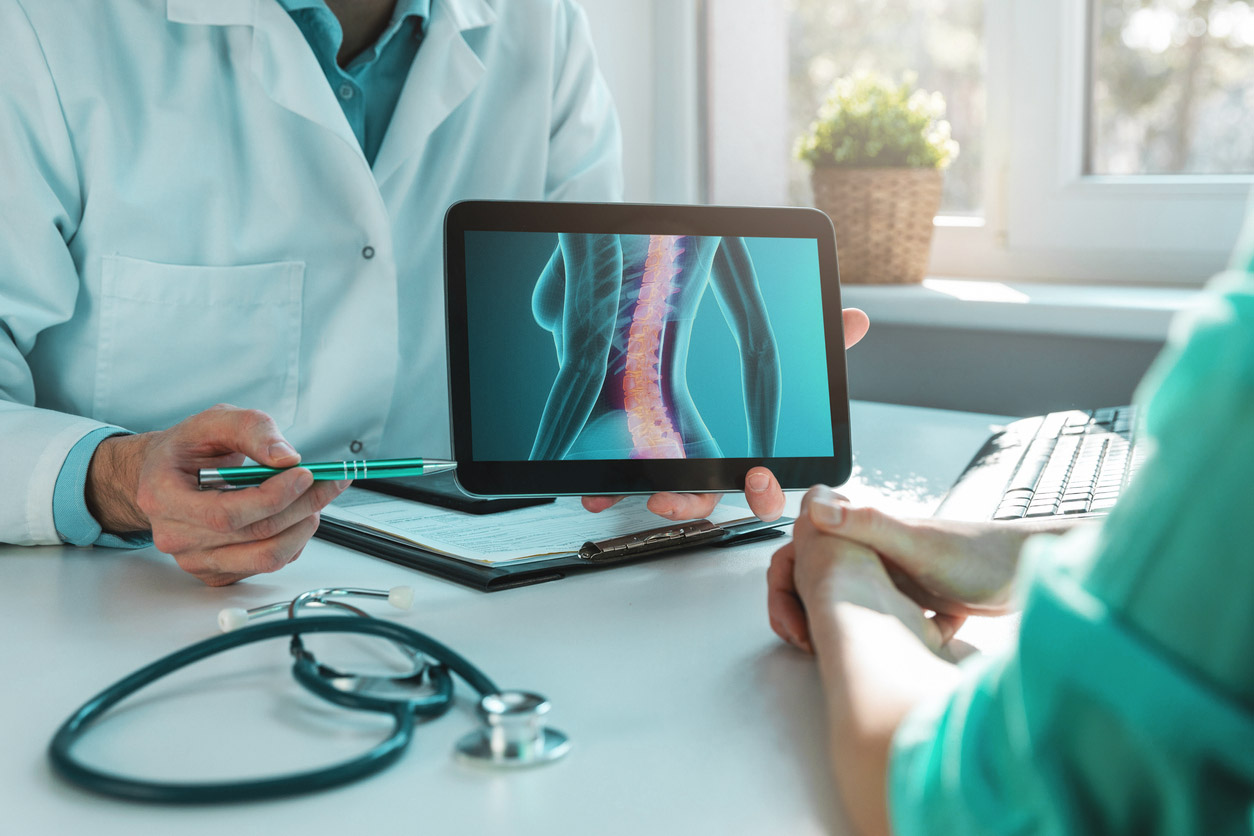

Sua coluna é formada por vértebras (ossos), discos, medula (nervos), ligamentos e músculos. Uma lesão ou doença na coluna pode afetar um ou mais desses